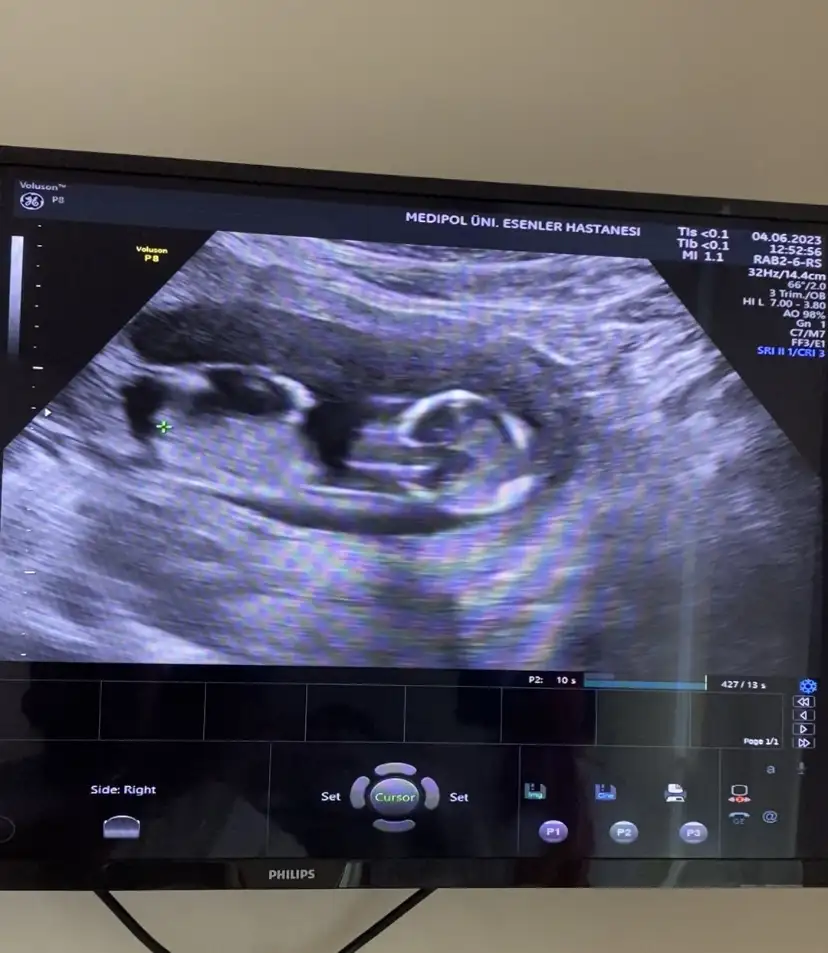

Bacak arası gibi ama çekimden mi bu kadar büyük bacakları, belki de değildir. Normalde böyle kalın ve kısa oluyorlarsoyasosu vu 14. Haftalıkken kendi doktorum 2. Bebegin poposunu görememişti ekrana sığmıyo diyerek bende videodan inceledim üstteki bebege bakarken alttaki bebegin bacak arası değilmi o benmi yanlış görüyorum

Vidodan baktım kesiin bacak arası canım ilk fotodakide bacak arası farklı bi açı orda çıkıntı var klitoris olsa 14. Haftada kaybolurdu heralde bilemedim iyiceBacak arası gibi ama çekimden mi bu kadar büyük bacakları, belki de değildir. Normalde böyle kalın ve kısa oluyorlarbaşka varsa atarsan bakarız birlikte

Burada hiç anlayamadımVidodan baktım kesiin bacak arası canım ilk fotodakide bacak arası farklı bi açı orda çıkıntı var klitoris olsa 14. Haftada kaybolurdu heralde bilemedim iyice

Devlet bişey vermedi görmedimde bugün kızda bacak arası daha boş ordan belli gibi kendi doktorum o gün kemik yapısına göre kıza benzettiğini söylemişti diğerini göremedim dedi ama videoda bi çıkıntı gördüm ben şimdi detaylı baktım cumartesi giderim netleşir inşallahBurada hiç anlayamadımama erkek olunca anlamak çok kolay oluyor. Videoda 3 çizgi belli mi kızda